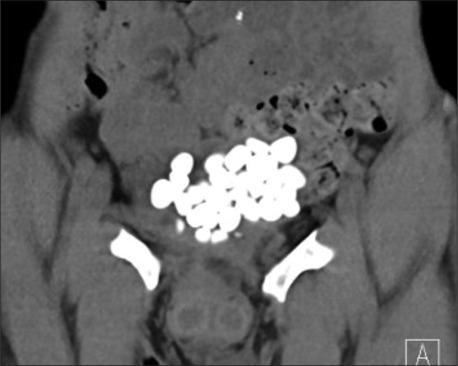

Results: Seven patients underwent a total of nine PCCLs between 2019 and 2023. Sone burden ranged from 4 to 10 cm. No intraoperative complications were faced. Three patients had residual stone fragments < 7 mm in size. Suprapubic catheter was removed between days 0 and 3 postoperative. Cystostomy was left to close spontaneously, none of the patients developed peritoneal leak after removal. Patients with Mitrofanoff channel reported no leak or compromise to the continued mechanism. Predominant stone composition was magnesium ammonium phosphate (struvite) in seven cases.

Abstract Image